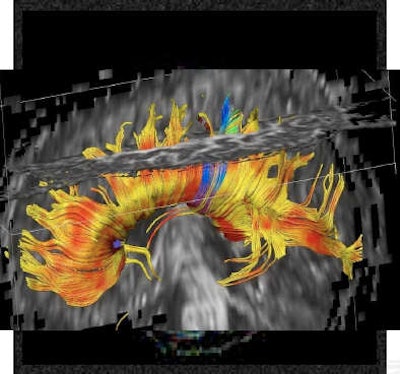

Diffusion-weighted imaging is proving valuable in cases of suspected ischemia. Diffusion-tensor imaging (DTI) involves fiber tracking and can evaluate the degree of anisotropy and maturation processes. All images courtesy of Dr. Birgit Ertl-Wagner.The growth in fetal MRI referrals to confirm and classify abnormal findings detected by ultrasound is also increasing diagnosis of prenatal conditions or diseases, as is its capacity to pick up additional abnormalities. Slight dilatation of the ventricles in an ultrasound may reveal severe intraventricular hemorrhaging or absence of the corpus callosum in MRI. This has significant prognostic implications and therapeutic consequences. The imaging expert's role in multidiscipline teams counseling parents on far-reaching decisions, such as termination of pregnancy or potential fetal surgery, should not be underestimated, Ertl-Wagner said.